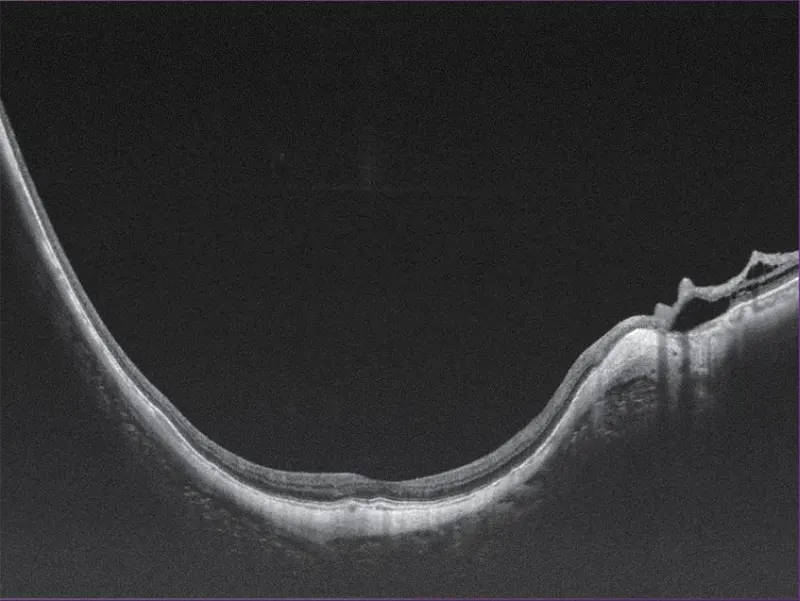

- Profundidad de escaneo de 12 mm, ideal para casos complejos como estafiloma miopía

Yalkaid (YG-100K) es una nueva generación de SS-OCT con una velocidad de 100 kHz. Su principal ventaja radica en la tecnología SS de rango completo, que permite una profundidad de escaneo de 12 mm para el vítreo, la retina y la coroides, y una extraordinaria de 15 mm para el segmento anterior. La resolución óptica de <6 micrones del dispositivo garantizan una observación detallada de las estructuras anteriores y posteriores.

Galería OCTs del TowardPi Yalkaid